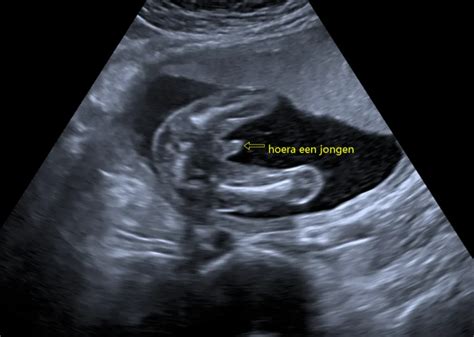

Echografie en vroege echo's

Naast consulten kunt u bij ons ook terecht voor echografie. Indien gewenst, maken we de eerste echo rond de zeven weken zwangerschap. Deze echo, die niet tot de standaard zorg behoort, dient ter bevestiging van de zwangerschap, controle van de locatie van de zwangerschap en om te bepalen of het om een eenling- of meerlingzwangerschap gaat. Wij bieden deze echo aan als extra service.

De eerste controle vindt plaats rond 10-12 weken zwangerschap. Een vroege echo rond 7 weken is mogelijk, maar behoort niet tot de standaard zorg. Tijdens deze echo, bedoeld als bevestiging van de zwangerschap, wordt gekeken of de zwangerschap zich in de baarmoeder bevindt en of er een of meerdere kindjes zijn. Ook wordt u geïnformeerd over prenatale screening.